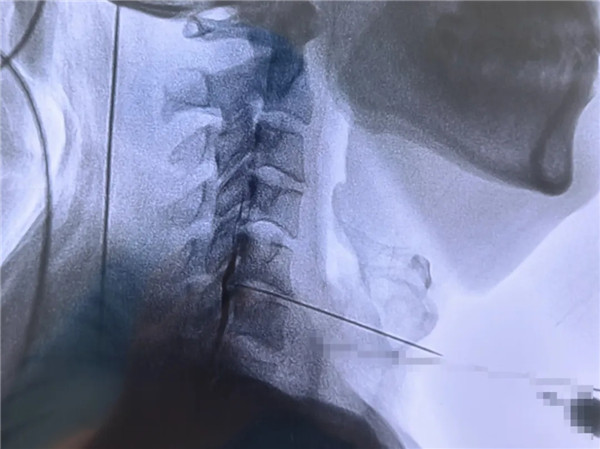

2年前,劉師傅出現左側肩背部疼痛,反復發作,影響正常生活,多次嘗試理療、藥物治療,疼痛未能緩解。經多方打聽,來我院骨四科就診。結合臨床表現及相關檢查,考慮到劉師傅的病情和對微創治療的需求,骨四科主任楊永輝帶領團隊經過充分討論,決定為其實施:頸椎間盤射頻消融、膠原酶溶解術。手術采用局部麻醉,僅通過一枚穿刺針,成功實施射頻消融、膠原酶溶解術,術口僅針眼大小。手術過程劉師傅一直清醒:“沒想到這么快就做完了!也不痛,效果蠻好!”術后第一天查房,左頸肩部疼痛明顯緩解,劉師傅連聲感謝:“現在寶雞市人民醫院的技術太好了,不用開刀也能解決頸椎間盤突出的問題!”

頸椎間盤微創射頻消融聯合膠原酶溶解術是頸椎間盤突出癥的一種微創聯合治療方式,通過兩種技術的協同作用達到更好的治療效果。射頻消融先快速收縮部分突出組織,為膠原酶創造有利的作用環境;膠原酶進一步溶解椎間盤內的膠原蛋白,鞏固和增強減壓效果,形成“1+1>2”的協同作用,相比單一技術更能有效緩解頸肩痛、上肢麻木等癥狀。

1.創傷小:手術通過穿刺完成,僅留下針眼大小的創口,無需開刀,避免了開放手術對氣管、食道、血管、肌肉的剝離和牽拉,對周圍組織損傷極小,術后恢復快,感染風險低。

2.安全性高:在局部麻醉下進行,患者術中意識清醒,可及時反饋感受,醫生能更精準地操作,減少對神經、血管等重要結構的誤傷。

3.療效確切:兩種技術協同作用,射頻消融通過熱凝收縮突出組織,膠原酶特異性溶解椎間盤內膠原蛋白,雙重作用下能有效減輕椎間盤對神經根的壓迫,緩解疼痛等癥狀,多數患者術后癥狀可明顯改善。